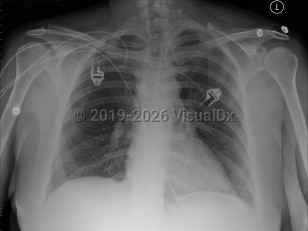

Cardiac tamponadeCardiac tamponade

Pericardial effusionPericardial effusion

PericarditisPericarditis